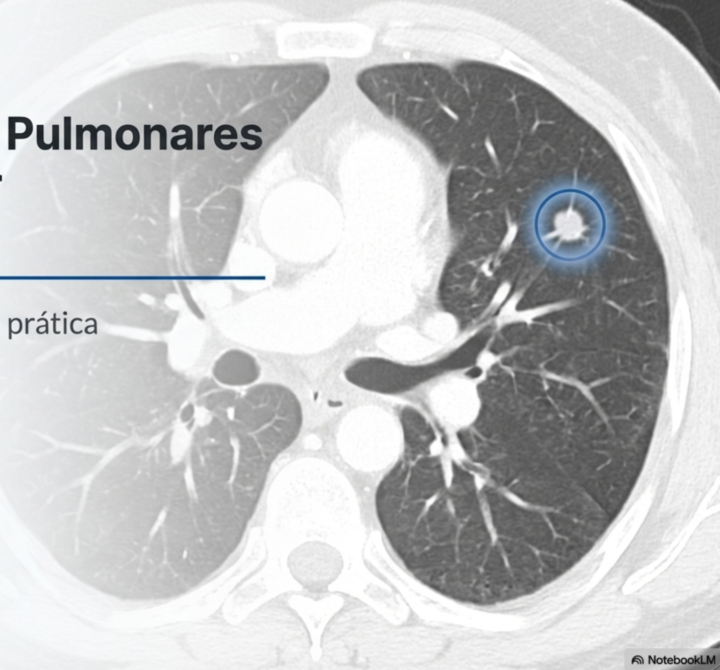

Histoplasmomas pulmonares assintomáticos (IDSA 2025)